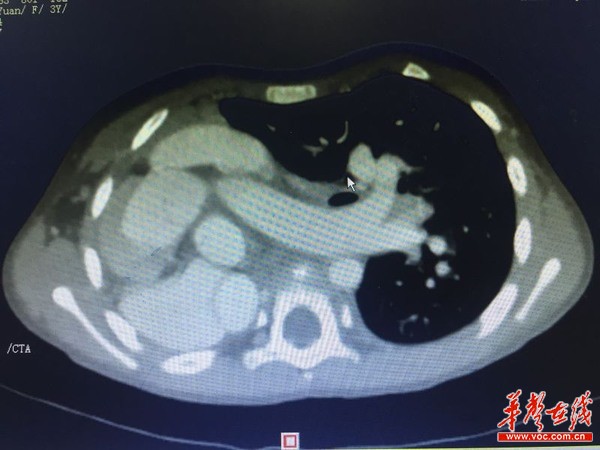

心脏CTA检查显示,巨大室间隔缺损、左肺动脉扩张、重度肺动脉高压。

为了寻求手术根治,2017年2月17日,家人带着瑶瑶来到湖南省人民医院心胸外科。心脏血管造影检查发现,由于右肺缺如,左肺将瑶瑶的心脏推移至右侧胸腔,室间隔缺损达13mm,导致严重的肺动脉高压,还出现左肺动脉和左肺静脉明显增粗。在这种情况下做手术的话,不仅手术难度巨大,术中极可能出现肺动脉高压危象,造成心衰,危及生命。